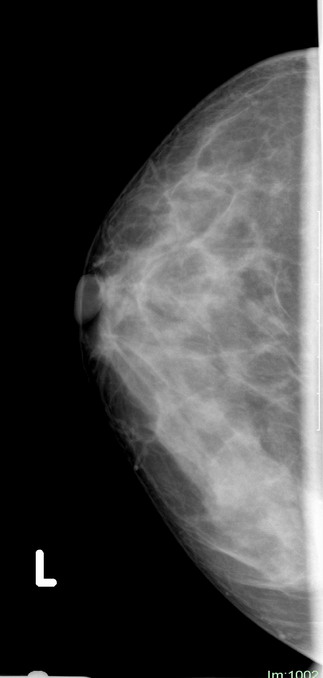

标题: x2364:女,45岁,乳房胀痛,触及硬块求诊 [打印本页]

女,45岁,乳房胀痛,触及硬块求诊

体查:左侧乳房可触及多个硬块,活动度可,无压痛

本人对于乳腺在太多的拿不准,发现乳腺太难看了,我的意见是:

1,左侧乳腺外上象限肿块样影,腺体增生?乳腺纤维瘤?

2,右乳外下象限局部密度增高明显,建议必要时彩超检查除外其他。

3,双侧乳腺小叶增生。

乳头稍凹陷,乳晕皮肤增厚,乳腺非对称性致密,未见明显肿块影,未见异常粗大血管和淋巴结

考虑双侧乳腺小叶增生症.

乳腺非对称性致密,未见明显肿块影,未见异常粗大血管和淋巴结